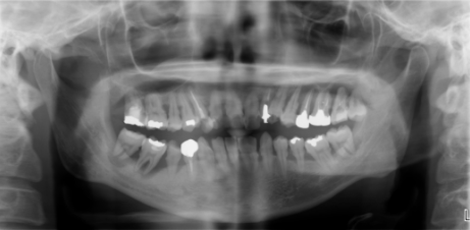

治療中

抜歯、インプラント、再生療法を行い、仮歯で様子をみてます。○○さん。もうすこしです。頑張りましょう。